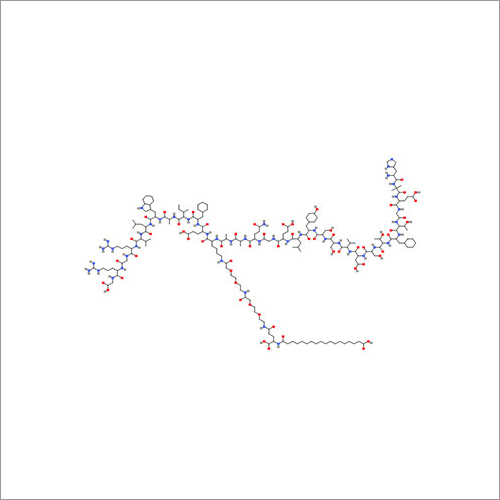

69558-55-0 थाइमोपेंटिन शुद्धता (%): > 99.0% (एचपीएलसी)

| रासायनिक नाम | Thymopentin |

| कैस नं | 69558-55-0 |

| रासायनिक नाम | Thymopentin |

| कैस नं | 69558-55-0 |